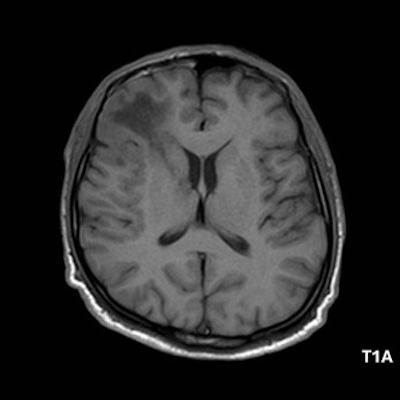

1. A) Aksiyel T2A görüntülerde bilateral sağda belirgin frontoparietal subkortikal ve derin periventriküler beyaz cevherde subkortikal U fiberleri boyunca yerleşimli sinyal artımları (oklar) izlendi.  Tarifli alanlar aksiyel T1A serilerde hipointens görünümde (oklar) izlendi.

1. PML’de MRG bulguları genellikle multifokal, asimetrik periventriküler ve subkortikal beyaz cevher tutulumu şeklindedir. Subkortikal U-fiberleri sıklıkla tutulur, özellikle parietooksipital bölgelerde belirgin lezyon eğilimi vardır.

2. T1 ağırlıklı görüntülerde tutulan bölgeler hipointens, T2A’da ise hiperintens izlenir. Ana lezyon çevresinde çok sayıda noktasal (milkyway) sinyal artımları görülebilir. Ayrıca spleniumu çaprazlayan parietooksipital sinyal değişiklikleri (barbell bulgusu) ve dentat nukleusu koruyarak serebellar beyaz cevher tutulumu (shrimp bulgusu) da tanımlanmıştır.

3. Kontrastlı incelemelerde genellikle kontrast tutulumu izlenmez. Diffüzyon görüntülemede özellikle lezyonun ilerleyen periferik alanlarında yamalar halinde diffüzyon kısıtlılığı izlenir. MR spektroskopide NAA azalması, laktat varlığı ve artmış kolin ve lipid düzeyleri görülür. MR perfüzyonda ise lezyonların ilerleyen kenarında perfüzyon artışı saptanabilir.

4. Bizim hastamızda bilinen HIV enfeksiyonu mevcuttu ve yapılan kraniyal MR görüntülemede multifokal, asimetrik, periventriküler ve subkortikal beyaz cevherde yerleşimli, kitle etkisi göstermeyen ve kontrastlanmayan lezyonlar izlendi. Lezyonların subkortikal U-fiberleri tutması ve özellikle parieto-oksipital bölgelerde belirgin olması nedeniyle ön planda PML düşünüldü. Histopatolojik tetkik ile PML tanısı doğrulandı.